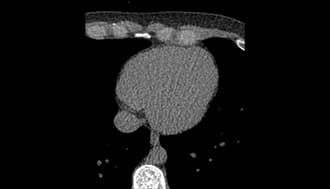

Full-Body MRI

Scans your entire body for cancers and structural issues.Detects problems early without any radiation.

CT Calcium Scoring

Checks for calcium buildup in your heart’s arteries. Identifies early signs of heart disease before symptoms appear.